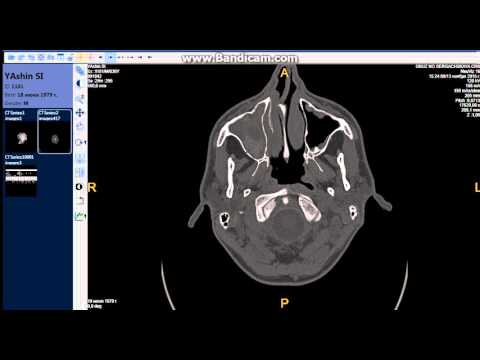

При недостаточной информативности рентгенологического снимка дополнительно может быть назначена компьютерная топография (КТ).

Рентгенологическое исследование костной структуры носа

При расшифровке рентген снимка костной структуры носа берется во внимание форма и дефекты строения костей. При выявлении трещин или переломов определяется их точная локализация, размеры, направление. Если есть костные обломки: указывается их локализация относительно костей или мягких тканей. По аналогичной схеме оцениваются инородные тела, обнаруженные на снимке и дефекты структур костной ткани (увеличение ее плотности или резорбция, новообразования).